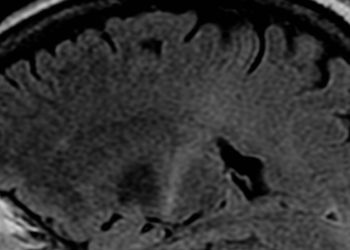

Image: PD